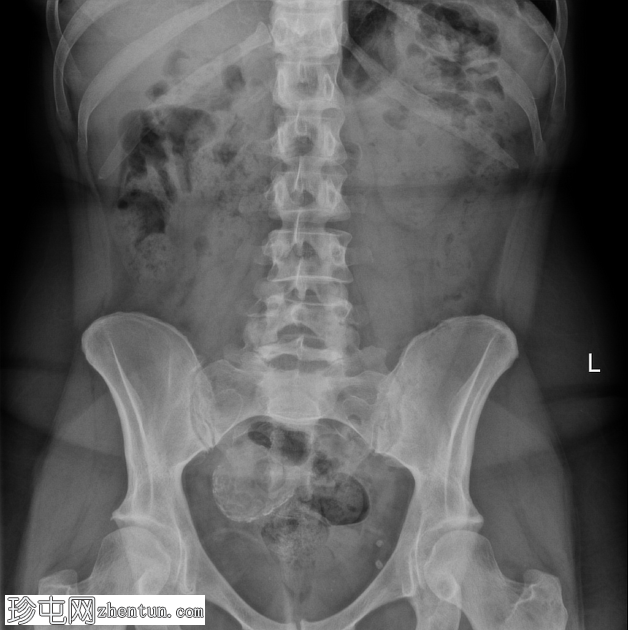

X线片

盆腔右侧可见一圆形钙化肿块,符合钙化性子宫肌瘤的影像学表现。

盆腔左侧可见两处小的圆形钙化影,符合盆腔静脉石的影像学表现。

后续盆腔超声检查证实子宫内存在钙化性子宫肌瘤。

子宫肌瘤(平滑肌瘤)发生钙化时,有时可在腹部或盆腔X线片上发现。此时,钙化灶通常粗糙不规则,常被描述为“爆米花样”外观。

“爆米花样钙化”是指致密、无定形的钙沉积物,呈环状或弧状排列,形似爆米花。虽然这种影像学特征通常与钙化性子宫肌瘤相关,但也可见于多种其他疾病,包括: